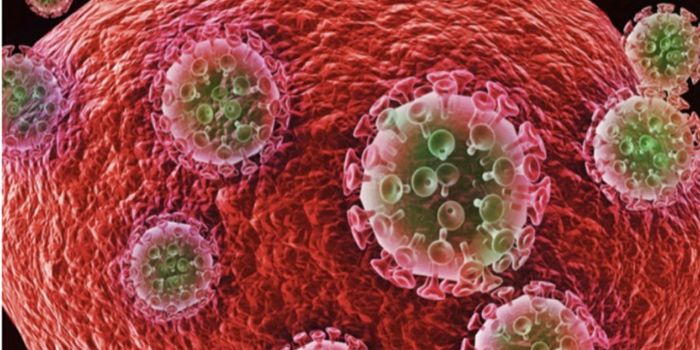

AUG 24, 2020ImmunologyOnce in the body, HIV tracks down T cells that bear the CD4 receptor. It attaches to these immune cells, fusing itself w ...

NOV 17, 2020ImmunologyLast year, around 1.7 million people became infected with HIV, with around half of these being women. Encouraging result ...

AUG 14, 2022ImmunologyFor the second time this year and only the fourth time ever, researchers have announced that a person has been cured of ...